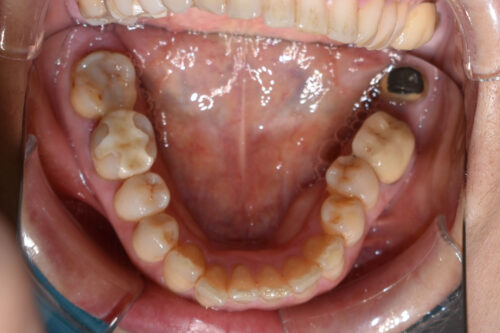

初診時年齢 46歳 女性

歯のでこぼこ(叢生)

左側完全クロスバイトの治療を

左側の小臼歯部から

大臼歯部にかけて

クロスバイトを呈し

過蓋咬合の状態でした。

ワイヤー矯正治療1年2か月後です。

全額矯正治療 88万円、3~4週に一回来院

歯科矯正用アンカースクリュー(デュアル・トップオートスクリュー)上顎左右2本(25000円x2本分 提携医院にて)

ワイヤー期間 14か月, 17回来院